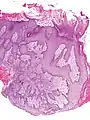

Microscopic image of the epidermis, which constitutes the outer layer of skin, shown here by the white bar | |

- Pseudoepitheliomatous hyperplasia (PEH) is a benign condition characterized by hyperplasia of the epidermis and epithelium of skin appendages,[33] with irregular squamous strands extending down into the dermis,[34] and closely simulating squamous cell carcinoma (SCC).[33]

Pseudoepitheliomatous hyperplasia (PEH), low magnification, with acanthotic squamous epithelium with irregular thick finger-like downgrowths into the underlying dermis.